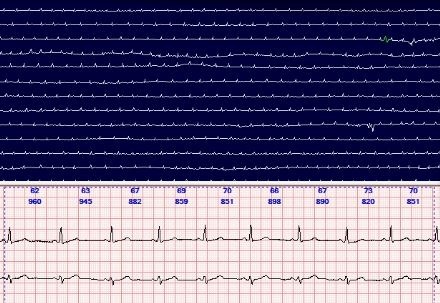

الکتروکاردیوگرافی پیوسته طولانی مدت یا سیستم نظارت هارتر

سیستم هولتر مانیتورینگ ECG : مدل My Patch & Vx3+

نسل جدید رکوردرهای هولتر ECG بدون نیاز به کابل بیمار ، باطری و چسلید .

ضبط 2، 3 و یا 12 کانال ECG تا یک هفته.

قابلیت تشخیص pacemaker (قابل استفاده برای بیماران دارای pacemaker )

امکان استفاده برای نوزادان زیر 10 کیلوگرم

ضدآب ، water proof

سهولت استفاده نسبت به دستگاه های دیگر هم برای اپراتور و هم برای بیمار با مطلوب ترین سازگاری با بدن بیمار

دارای 1 سال گارانتی و 10 سال پشتیبانی قطعات توسط شرکت اوسینا

نصب ، راه اندازی و آموزش رایگان برای کلیه مراکز در سرتاسر ایران